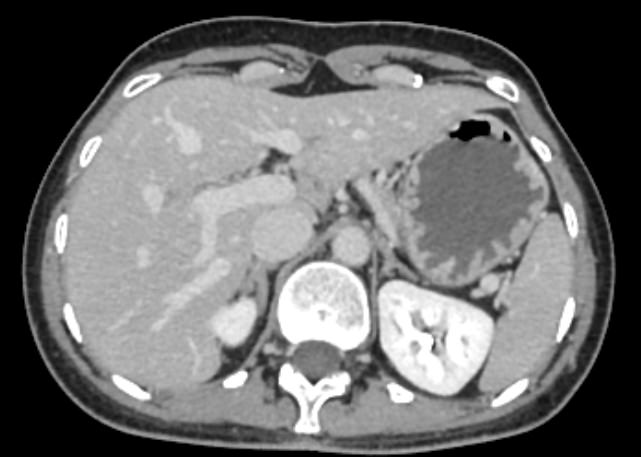

Для диагностики патологии нижней полой вены применяется высокоинформативный быстрый и неинвазивный (то есть не требующий вмешательства в организм пациента) метод исследования – мультиспиральная компьютерная томография (КТ-ангиография). КТ-ангиография позволяет диагностировать патологические изменения нижней полой вены на ранней стадии развития, когда лечение наиболее эффективно.

Метод компьютерной томографии основан на применении рентгеновского излучения. Источник излучения, расположенный в кольцевой части томографа, вращается вокруг зоны исследования и делает послойное сканирование со срезами толщиной от 0,5 мм. Для визуализации кровеносных сосудов обязательно используется контрастное усиление, которое усиливает контрастность сосудов на фоне окружающих тканей и позволяет увидеть патологические изменения на начальной стадии.

Для контрастирования используется йодсодержащий препарат, обладающий высокой рентгеноконтрастностью за счет способности поглощать рентгеновские лучи. Препарат вводится пациенту внутривенно во время исследования и позволяет диагностировать различную патологию нижней полой вены, включая аномалии развития, тромбозы, воспалительные изменения сосудистых стенок, опухолевые образования, прорастающие в нижнюю полую вену или сдавливающие ее извне.